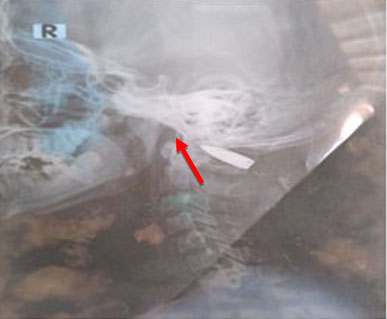

Figure 2: Standard cranio-cervical X-ray showing the presence of a projectile at the level of the occipito-atloid joint (red arrow).

Share Image:

We report the case of a 16-year-old patient from Guinea (Conakry), with no particular pathological history residing in the Medina that we had received two (02) months from a ballistic trauma of the upper cervical spine that occurred in Guinea Conakry. She allegedly received a projectile (gun bullet) in her home during an armed attack in her neighborhood at around 4 a.m. She presented with stiff neck with no other associated signs. The general examination revealed: a general satisfactory condition, skin and mucous membranes well colored, no edema of the lower limbs, nor folds of dehydration. The weight was 45 kg, the height 1.50 meters, the temperature 37.1 °C, the frequency: 90 beats/min, and the respiratory rate: 22 cycles/min. On neurological examination: walking was normal, there were no sensory-motor deficits nor genito-sphincter disorders. Examination of the spine revealed kyphosis of the cervical spine with contraction of the para-vertebral muscles on palpation. At the cephalic end, we noted the presence of a wound in the process of vertical healing, about 5 cm long, located at the level of the left posterolateral face of the neck, corresponding to the entry orifice of the projectile (Figure 1). The blood crisis was normal. The standard cranio-cervical radiography had objectified the presence of a projectile at the level of the occipito-atloid joint (Figure 2). Cranio-cervical computed tomography which revealed the presence of a projectile at the level of the left occipito-atloid joint with fracture of the internal cortical bone of the ipsilateral condyle (Figure 3). The aim of the surgery consisted of a cervical laminectomy associated with a withdrawal of the projectile (Figure 4) at the level of the condylo-atloid junction and an exploration in search of vascular complications (damage to the vertebral artery) and osteomeningeal breaches (dural lesion) that we had not detected during the operation. Wearing a C4 collar for a minimum of 3 or 4 months was associated. Postoperative parenteral treatment with amoxicillin-clavulanic acid (1 g × 2/d in direct intravenous (IVD)), hydrocortisone hemisuccinate (100 mg × 2/d in IVD= direct intravenous) and analgesics at a rate of 60 mg/kg weight divided into four doses are prescribed for four days, with an oral relay for eight days. The operative consequences were simple. The operative outcome was simple. The patient was seen again one month after surgery without any clinical particularity.

Figure 4: (A) Intra-operative image after extraction of the projectile showing the path of the projectile (yellow arrow); (B) Image of the projectile after removal of the ipsilateral condyle (white arrow).